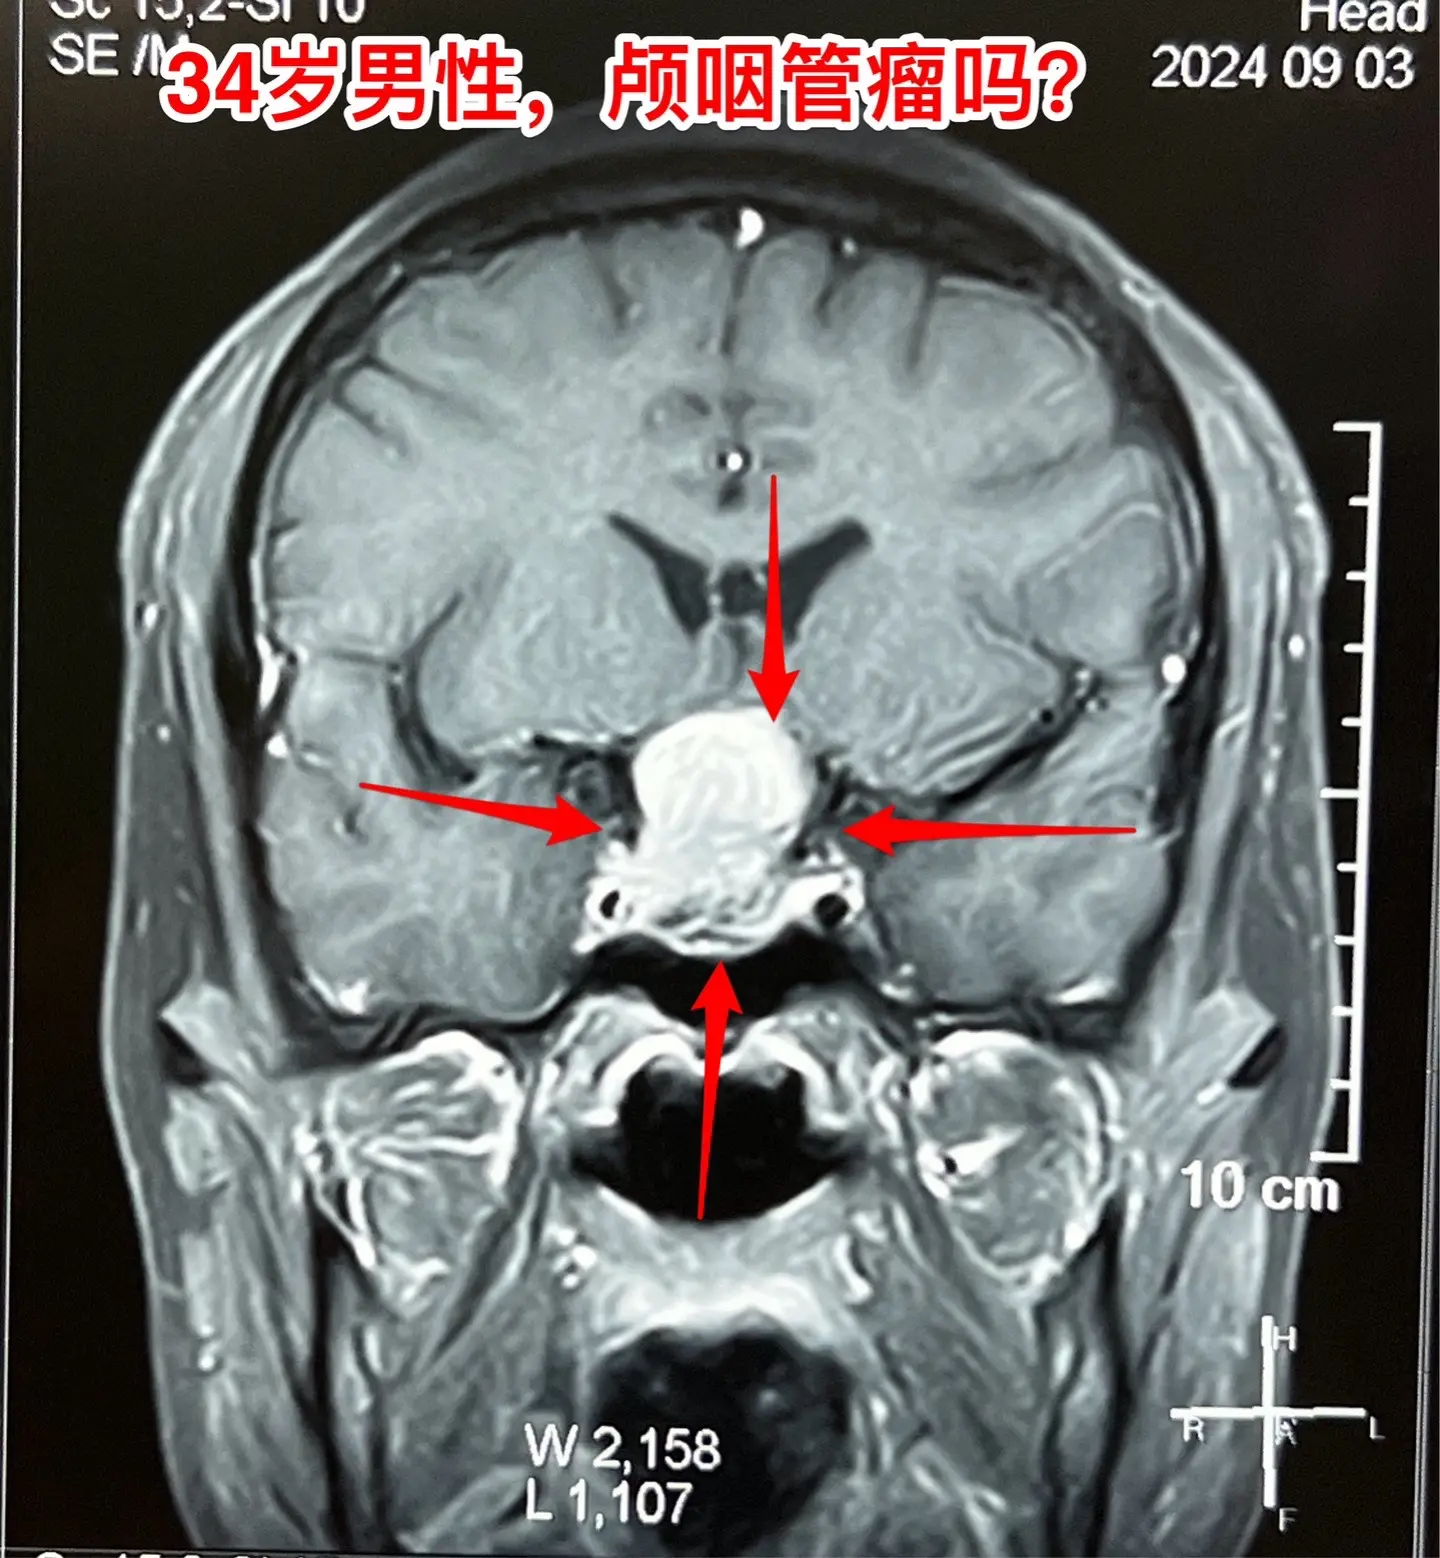

这是颅咽管瘤还是拉克氏囊肿?

我们把拉克氏囊肿放在第一位。有时候这两种病还是很难鉴别的。

手术后患者视力明显改善,精神也好转。9月12日出院了。病理报告就是拉克氏囊肿。